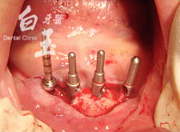

植入植體